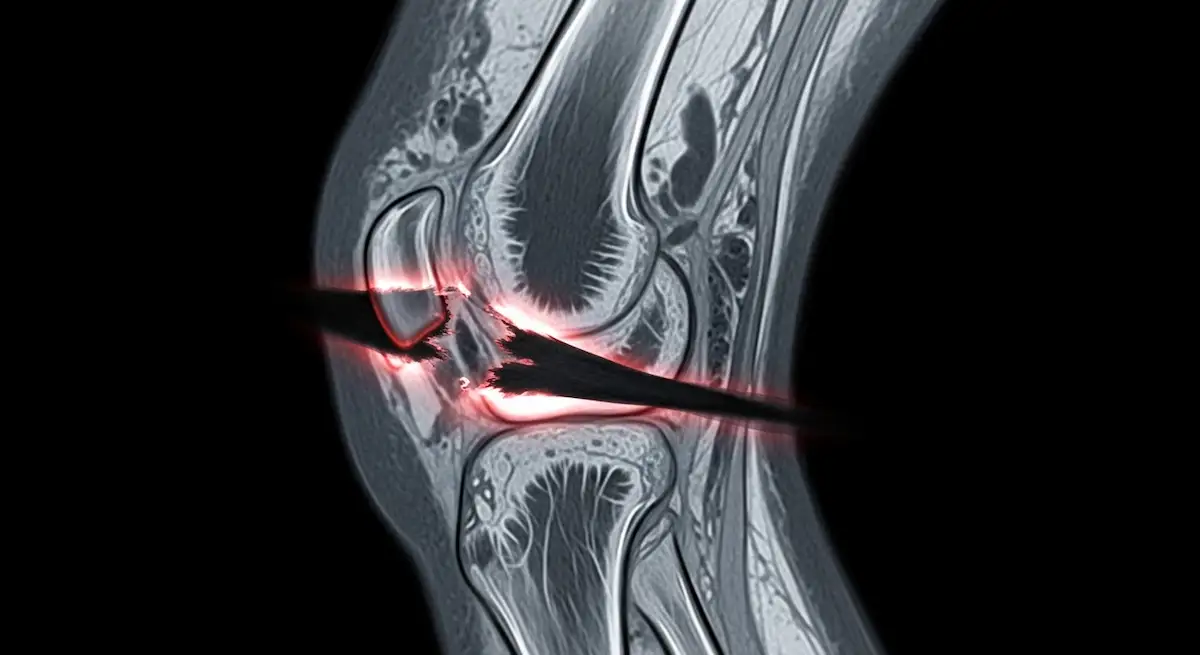

A ressonância magnética confirma as lesões do LCP e pesquisa lesões associadas, enquanto radiografias com estresse ajudam a medir o grau de translação posterior.